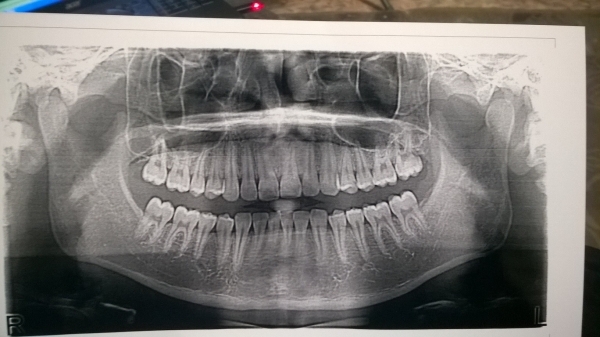

Поначалу думал кариес, записался к врачу на прием, он сказал, что не может сказать точно, что за болезнь, возможно зуб мудрости растет. Сказал сделать фронтальный снимок. На прием пойду только через 3 дня.

Хотел бы услышать мнение опытных врачей. Беспокоит боль с левой стороны. Когда трогаю ухо, оно чуть болит. Или когда рот открываю полностью, также присутствуют боли с левой стороны.

Если не смотреть снимок, то по симптомам действительно можно было предположить, что растёт восьмой зуб. Но по рентгену у Вас нет и зачатков зубов мудрости, может и не будет вовсе.

Одним словом, проблему надо искать на очном приеме. Зубы мудрости исключены.